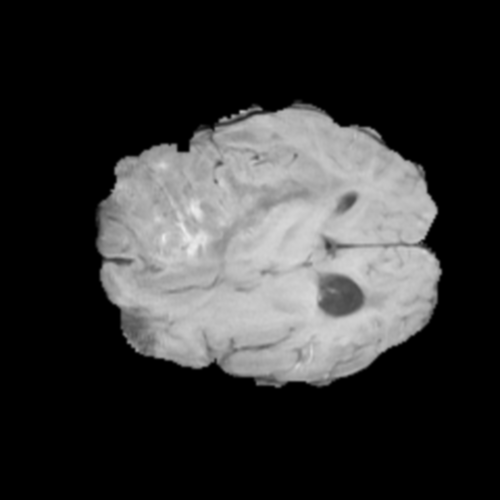

Ejemplos de Modalidades MRI

Visualización de las 4 modalidades de resonancia magnética y las segmentaciones de zonas tumorales utilizadas para entrenar el modelo

Glioma de Bajo Grado (LGG)

FLAIR LGG

FLAIR

T1ce LGG

T1ce

T2 LGG

T2

T1 LGG

T1